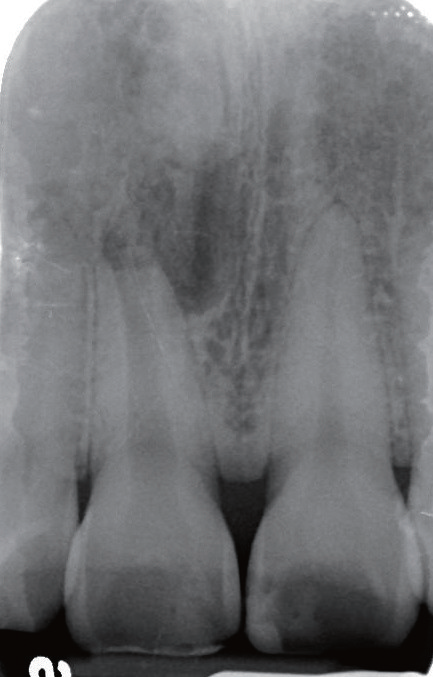

影像学检查   X线片显示11根尖尚未闭合(或根尖已经吸收),且根管宽大,可见根尖有一约8×10 mm的放射性阴影,周边牙槽骨明显缺损。询问患者自述曾经摔倒过,11受到撞击,不记得具体细节。

诊断与治疗计划   对比11 和12(图2)以及11和21(图3),11 的牙根长度较短,其根尖已出现阴影,按正常发育,11的根管应该不会如此宽大。因而推测患者在7~8 岁时,11应该曾经受到强烈撞击,导致牙髓坏死,使得根管没有继续钙化沉积,造成如今管壁相对较为单薄、根尖仍未完全闭合的情形。因而建议可在不给予局部麻醉下进行11开髓,进一步检查根管内部牙髓组织的实际状态。同时借助显微镜辅助进行根管治疗。

图2 对照12,11 根尖未闭合,牙根发育不全,且根尖周出现放射性阴影